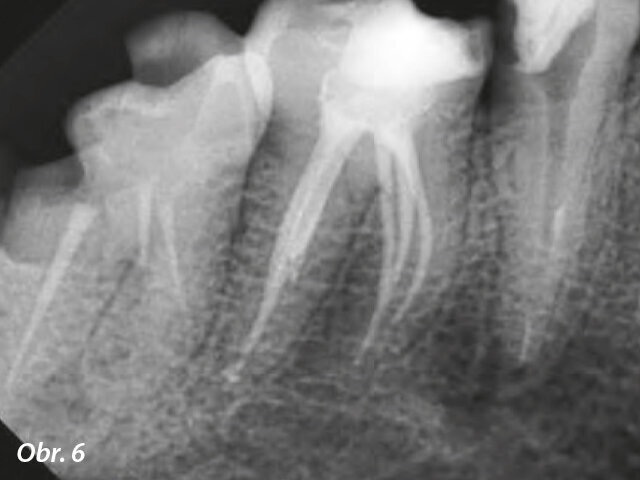

Preoperační rentgenový snímek zubu 46. Obr. 2: Meziálně excentrický rentgenový snímek s pěti viditelnými kořenovými kanálky.

Posledním krokem bylo vytvoření správného utěsnění, které zabrání mikroorganismům v opětovném vstupu do systému kořenového kanálku a chrání kořen před případnou rekontaminací. Pro efektivní a trvanlivou obturaci jsme vybrali techniku hydraulické kondenzace GuttaFlow Bioseal (Coltene) (obr. 5). Obturační materiál „tři v jednom“ kombinuje tekutou gutaperču s vhodným sealerem a biokeramiku v injekční stříkačce Automix. Výsledkem tohoto složení je snadno manipulovatelný materiál s vynikajícími tokovými vlastnostmi a dobou zpracování od 10 do 15 minut. Gutaperča je zahřátá a může být kondenzována dolů pomocí pluggeru, pokud ještě nezačala proudit do všech (i skrytých) samostatných kanálků. Po polymeraci tvoří bioaktivní materiál na povrchu krystalky hydroxyapatitu, což výrazně zlepšuje adhezi a aktivně podporuje regeneraci kosti a dentinu. Pooperační rentgenový snímek zobrazuje mohutnou „chobotnici“ s jasně rozpoznatelnými rameny, všemi spolehlivě zaplněnými gutaperčou (obr. 6). Dlouhodobá dokumentace potvrdí, jestli se nám podařilo vytvořit trvanlivé utěsnění kanálků.